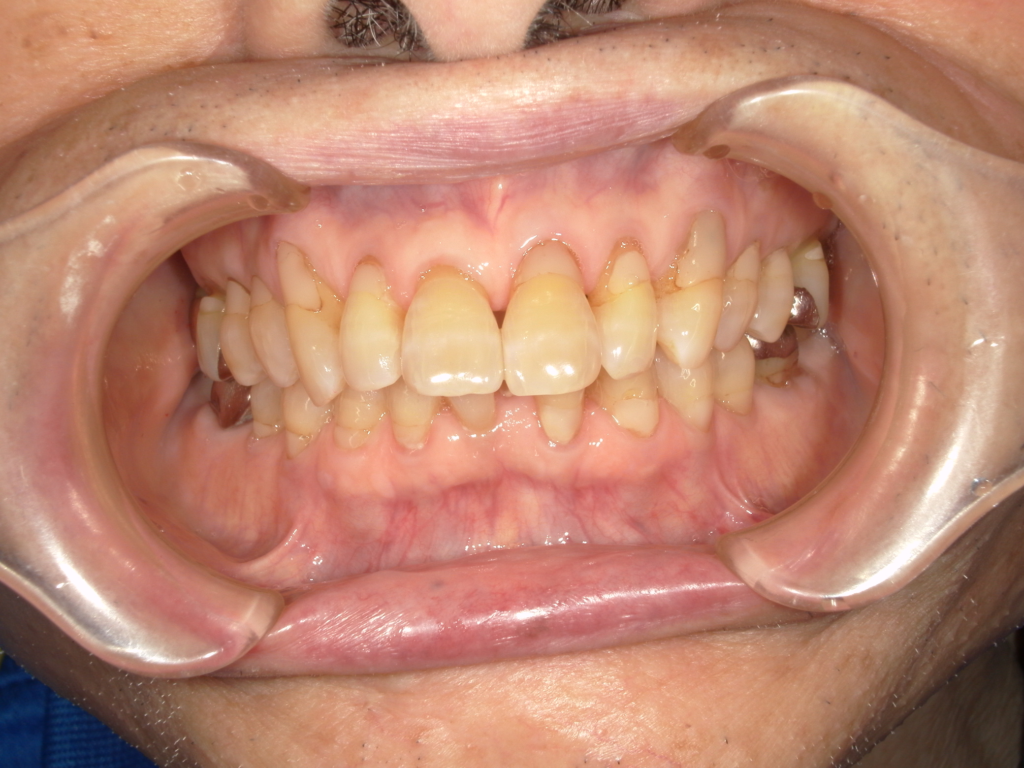

Y様インプラント実例 #44

左の上下の奥歯をインプラントで治療しています。

左下の奥歯は歯を抜くのと同時にインプラントの埋め込みを行っています。

被せものは上下、セラミックスで作っています。

治療前

治療後